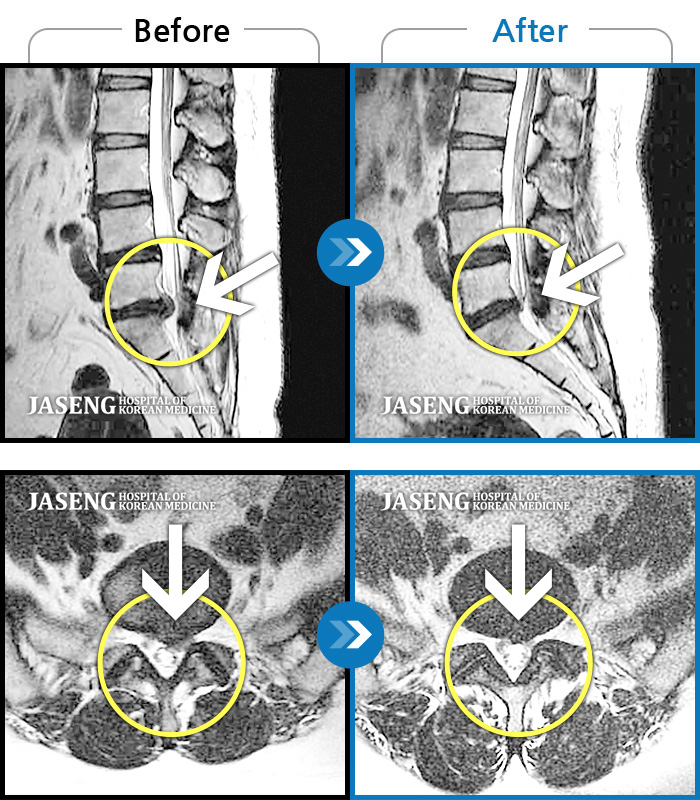

허리디스크 2단계(초기) 진단을 받긴 했으나 다행히 근육량이 많아 모르고 살았는데 사고로 인해 디스크에 상처가 생겨 힘든 나날을 보내고 있습니다

70대 어머니가 디스크파열로 수술을 당장해야한다는 큰병원의 권유를 뒤로하고 자생을 결정하고 엄봉군원장님을 만났습니다. 두달여 치료받고 많이 호전되었고 갈때마다 진심을 다하시는 원장님으로 인해 정서적인 치료도 받고 있답니다 앞으로도 잘 부탁드립니가!!

디스크수술만 두번했어요 사고때문에 생긴 통증때문에 걱정이 많았어요 엄원장님 설명도 알기쉽게 해주시고 환자에대한 배려가 참 많은 분이셔서 많은 도움을 받고있습니다 적절한 치료처방으로 상태도 많이 호전되어 더 신뢰가가고 너무 감사해요 이렇게남아 감사의 글을 드립니다